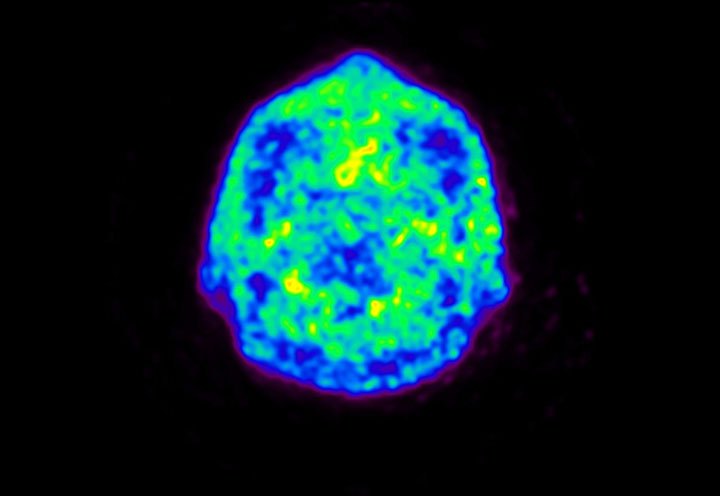

Head / Case5 : Amyloid

Courtesy : Kindai University Hospital

- Imaging protocol

- Injected dose: 4.27 MBq/kg, 18F-Flutemetamol

- Uptake time: 99 minutes

- Scan time: 20 minutes